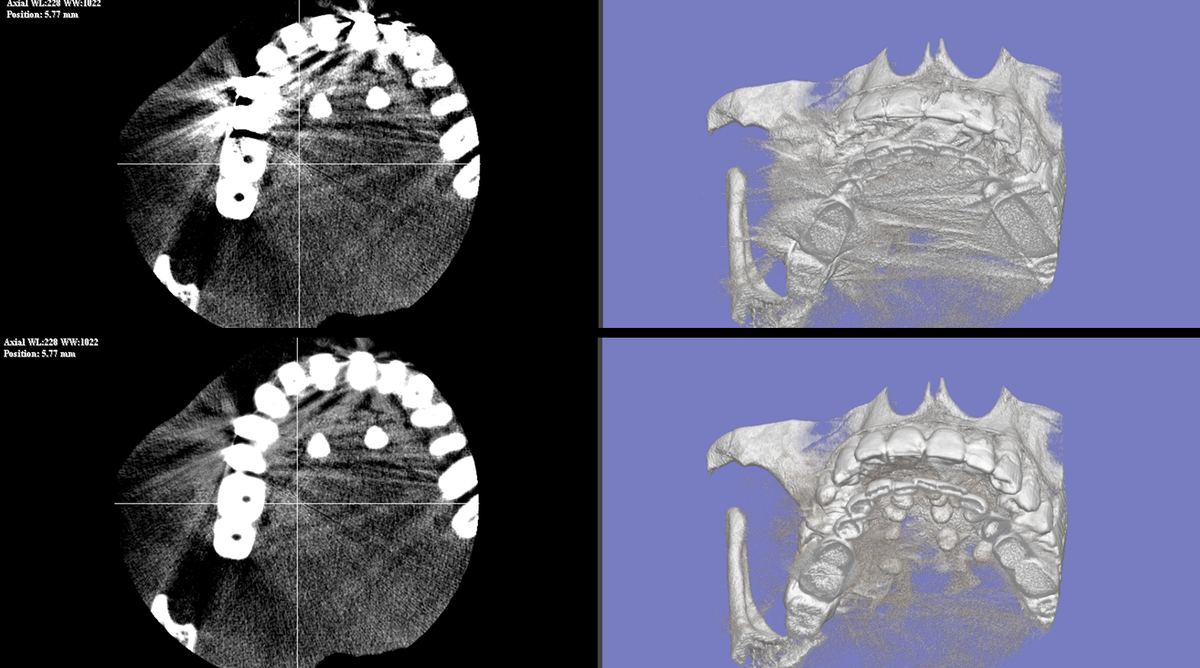

症例 B 上段: Before / 下段: After

D-MAR 症例B Before/After